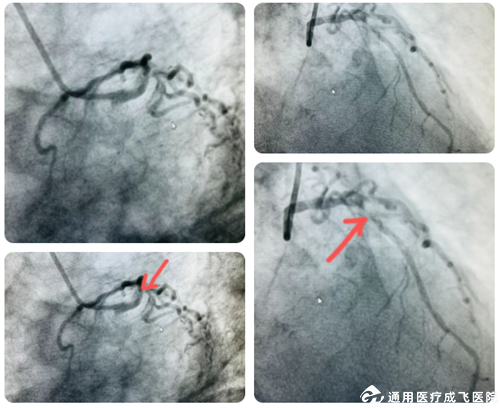

80岁的任大爷有多年高血压、糖尿病史,近一年来,他时常感觉胸前区闷痛,在成飞医院经冠脉造影及血管内超声发现:左冠状动脉病变严重,前降支近中段、左主干尾部可见270-360°环形内膜严重钙化,左主干尾部及前降支近中段斑块负荷达80%-90%。这些包绕血管的钙质就像禁锢在血管管腔上的“盔甲”,冠脉钙化与多种心血管疾病密切相关,然而相应的介入治疗手段却很有限。血管钙化使管壁变硬,顺应性降低,导致传统介入器械通过难度大,容易引发支架脱落、膨胀不全、纵向压缩,以及导丝断裂等并发症,影响治疗效果,因此成为介入治疗的难题。

术前